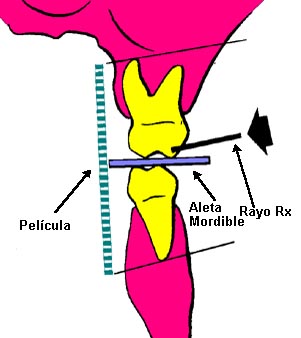

Radiografía de aleta mordible

(Bite-Wing)

La técnica tiene ventajas

con respecto a la radiografía periapical, debido que

reduce el tiempo de exposición a la radiación y disminuye

los costos y honorarios.

Técnica:

La cabeza del paciente se

coloca de manera que el plano de oclusión quede paralelo al del

piso. El rayo central se dirige al punto de contacto de los

dientes superiores con los dientes inferiores y paralelo a sus

superficies proximales, con el tubo formando un ángulo de 5 a

10º por encima del plano horizontal.

Ver figura 5. Para los dientes posteriores es

deseable tomar dos vistas de cada lado:

-

una en la que la película

se coloca más atrás para incluir el espacio inter-proximal

entre el segundo y el tercer molar,

-

y la otra lo bastante adelante

como para tomar la cara distal del canino. Solo necesita cuatro

películas para el diagnóstico de caries en todos los sectores

posteriores.

-

Cuando el tercer molar se

encuentra en proceso de erupción y se observa solo una parte de la

corona clínica a la inspección visual, es de utilidad diagnóstica

general, una imagen de una radiografía periapical de esa pieza

dental en particular.

Figura 5 |